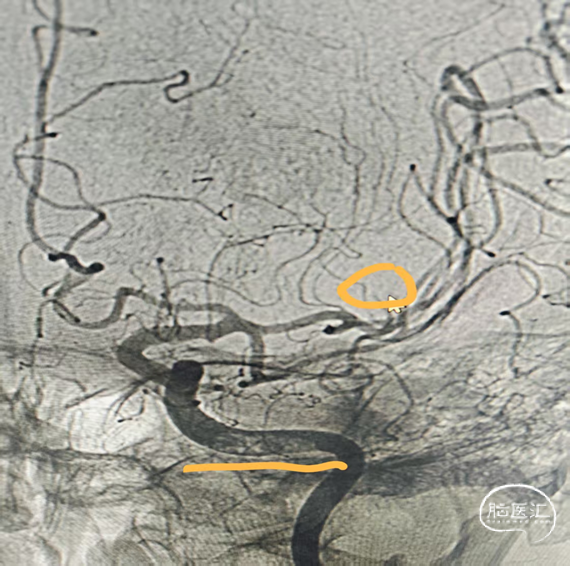

急诊DSA:

左侧颈内动脉C3段附壁血栓形成,左侧大脑中动脉M2段上干分支串联闭塞。

左侧大脑中动脉上干M2、下干M5段多发栓塞。

左侧椎动脉无向左侧大脑半球代偿供血。

前交通未见开放,未向左侧大脑半球代偿供血。